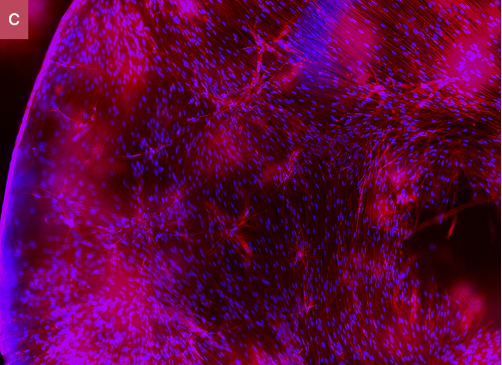

Fluorescent micrographs of 3D cell culture of human fibroblasts within Collink.3D™ 90 hydrogel. Cells are fixated and stained with Hoechst and RFP. A. Fibroblasts invasion and migration into gel matrices five days after seeding: commercial standard. vs. B. Collink.3D™ 90. C.Fibroblasts embedded in Collink.3D™ 90 spheroid after a week of incubation at 37 °C.